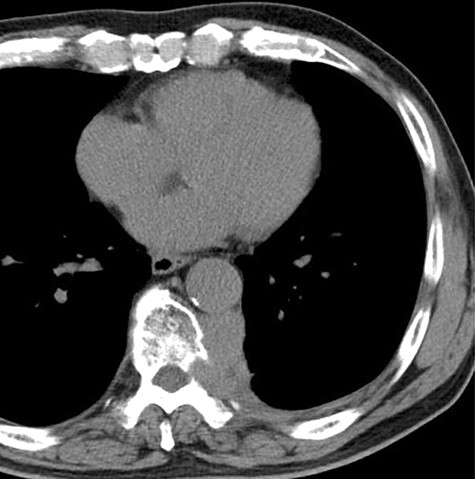

A 78-year-old man complained of chest pain for 2 months and was admitted to our hospital. Computed tomography (CT) scans revealed a tumor in the left thorax. He had undergone prior surgical resection of the primary SFT and recurrent tumor at 11 and 2 years before the current presentation. The CT findings of the primary tumor revealed a solitary, well-circumscribed and no signs of invasion (Fig. 1). Intraoperatively, the primary tumor arose from the visceral pleura and the resection was performed by wedge resection. The resected tumor was an oval, elastic soft mass with homogenous milky white cut surfaces. Postoperative histopathologic and immunohistochemical findings were consistent with SFT, and the mitosis and malignant features, including nuclear atypia, necrosis or higher cellularity, were hardly seen. In contrast to the primary tumor, as shown in Fig. 2, the CT findings revealed that the current tumor extended through the neural foramen. Furthermore, the tumor had an osteoclastic progression into the thoracic spine. Therefore, this tumor was considered to become malignant, and we considered the surgical complete resection is impossible. For histological confirmation, CT guided needle biopsy was performed. The histological findings of this recurrent tumor were identical to those of the primary tumor. The mitosis was hardly seen in this recurrent tumor. However, immunohistochemically, the MIB-1 proliferation index (Ki-67) of the primary tumor and the current tumor was 1.74 and 30.00%, respectively (Fig. 3A and B).

The computed tomographic findings of the current tumor; note the tumor extended through the neural foramen, and had an osteoclastic progression into the thoracic spine (arrow).